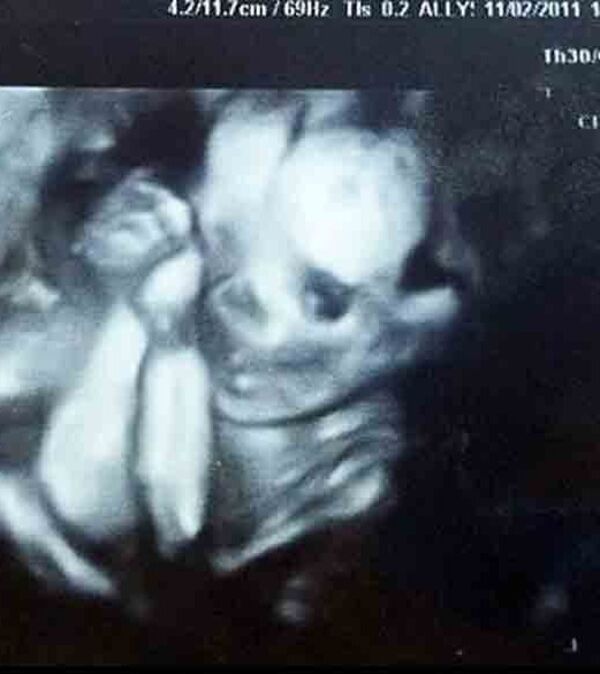

Bebekler anne karnında ne yapar?